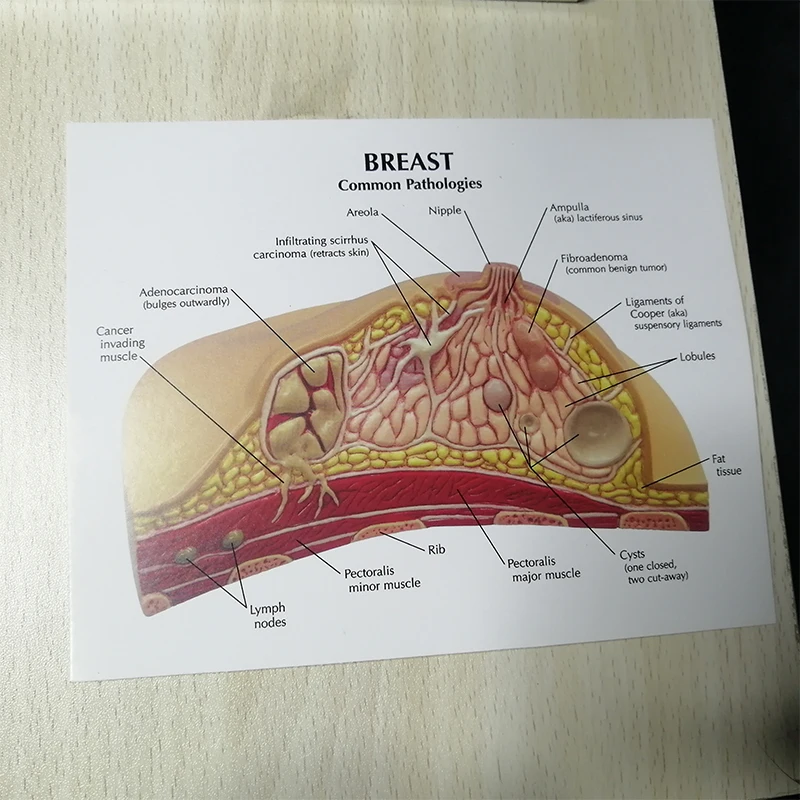

Аномалии молочной железы: медицинские примеры и визуализация

Раздел: Мудрость в деталях